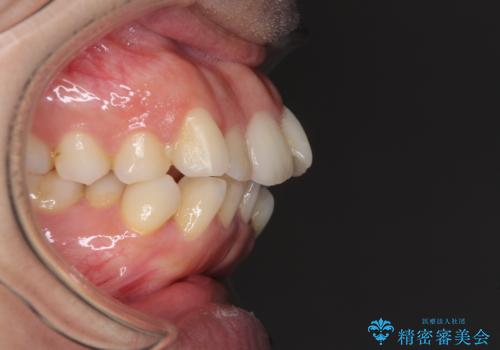

- 前歯のデコボコと口元の突出感を気にして来院された患者様です。

上下左右第一小臼歯4本を抜歯し、ワイヤー装置にて口元を引っ込めるよう矯正治療を行うこととしました。

叢生が強かったため、口元の突出感の改善には限界がありましたが、横側からも口元が引っ込んだ感じが分かるほど改善されました。